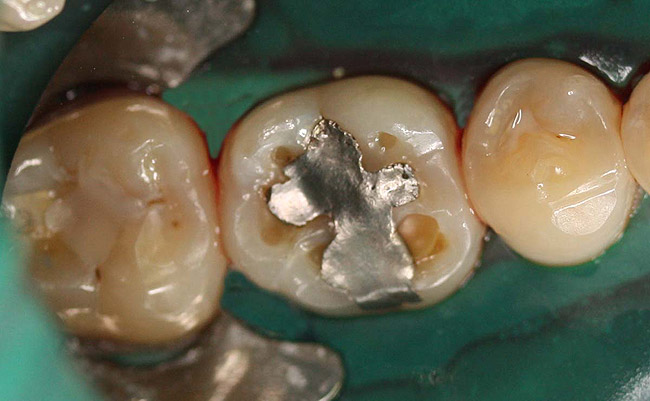

Case 2 (Figure 7 through Figure 11) depicts a series of defective amalgams on the first molar and biscupids. The amalgams were removed, the decay was excavated and cracks were eliminated. Bonding was completed on dentin and enamel. The teeth were matrixed and composite was built with layering techniques. To control contours, each tooth was completed individually, and then the next one was done. Composite was shaped, occlusal adjustment was completed, and final polishing was done.

Figure 8. Teeth after removal of amalgams.

Figure 8